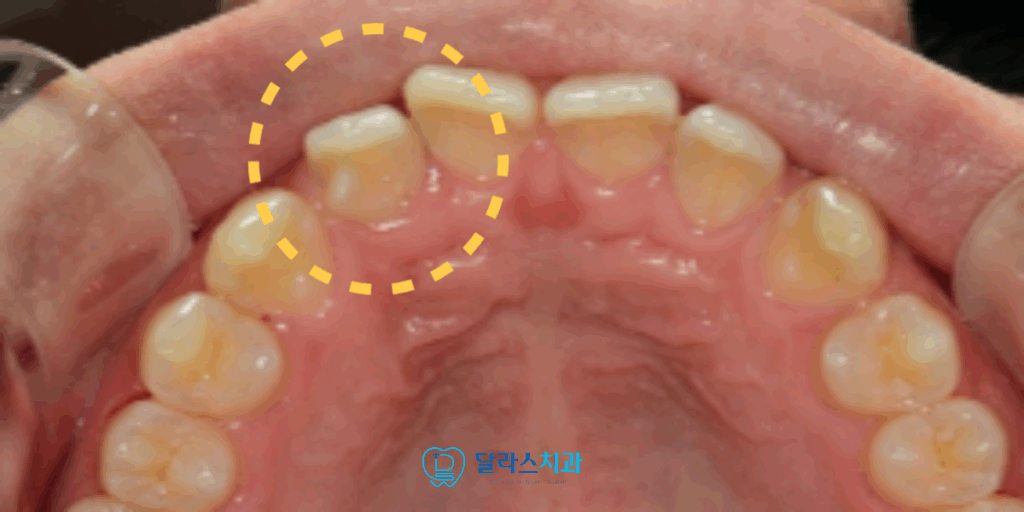

오른쪽 위의 두 번째 앞니를 보면 치아의 모양이 기형적인 것을 확인할 수 있습니다.

이 기형치로 인해서 교합관계가 방해를 받아서 정상적으로 물리지 않고 있었습니다.

동시에 #12 치아에는 crown 치료를 시행하여 palatal cusp이 발달된 것을 조정하였으며,